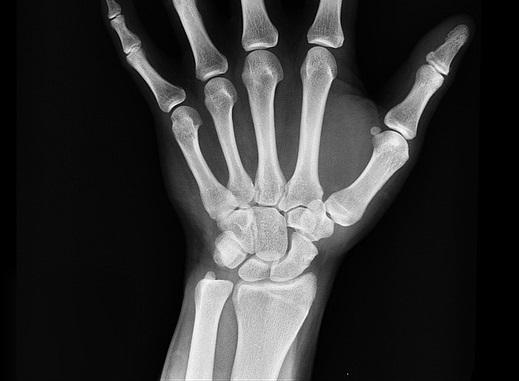

Ensaio clínico randomizado comparou o uso de imobilizações rígidas com simples bandagem quanto aos níveis de dor e função em fraturas da região distal do rádio.